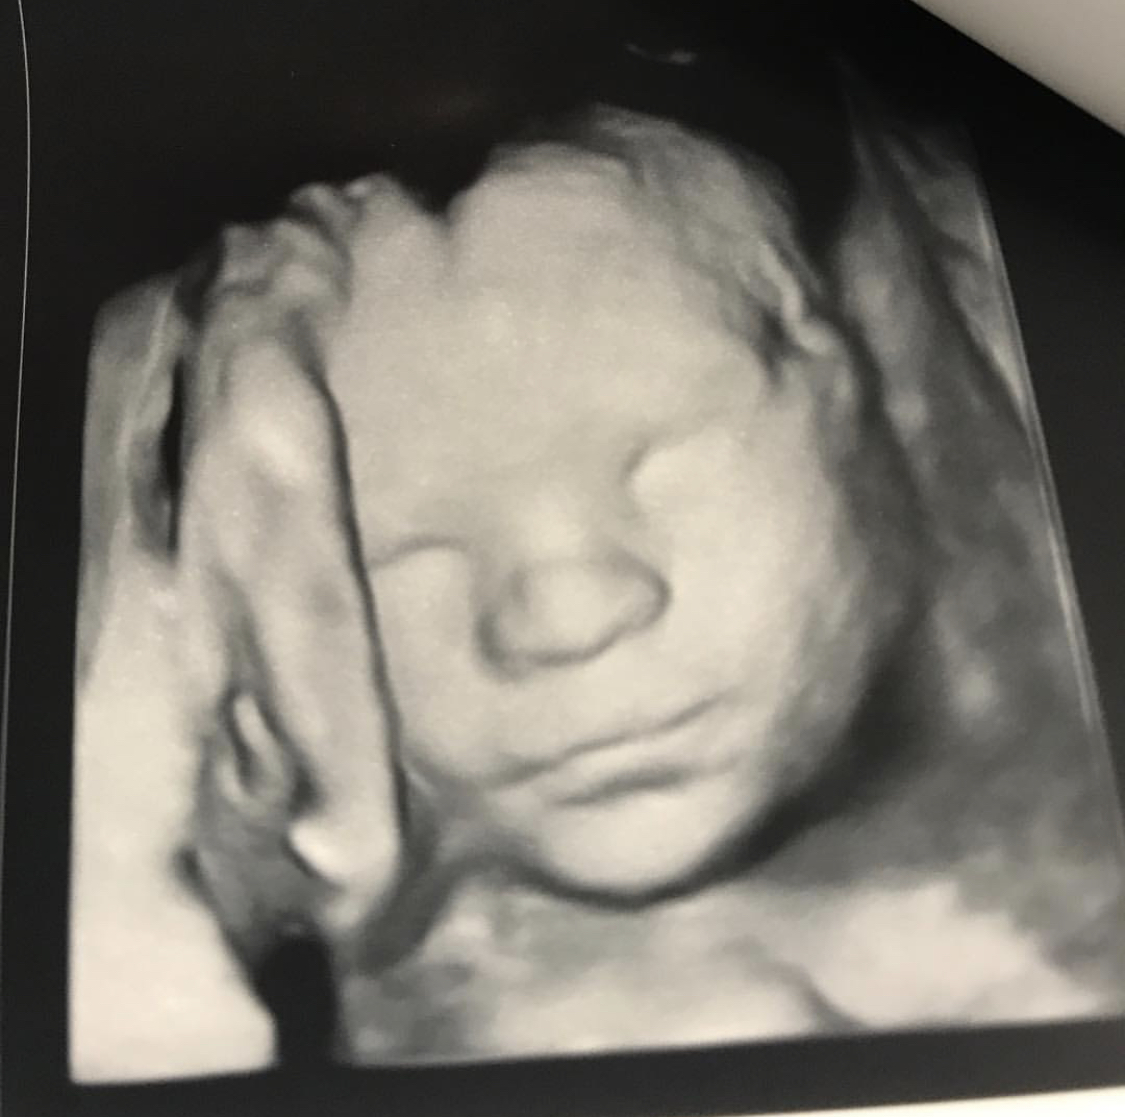

I didn’t call my OB until I was about 16 weeks because well…#notmyfirstrodeo. My first scheduled appointment was for my 20 week ultrasound, we’d get to see our baby + find out the gender! I wanted to be surprised but Ty can’t handle it. He has to know, he can’t stand the suspense! The second the sonographer put the doppler on my belly it landed right on a certain area and I knew our baby was going to be a boy! We were thrilled, although we didn’t have a preference whether God gave us another boy or girl, but we knew Lincoln was going to be ecstatic. He’d be praying about this day for many years. Finally…another boy in the family!

Fast forward 2 weeks, we had another scan with the same results. 2 weeks later, same results. We were going in for ultrasounds every 2 weeks for about 12 weeks, each time more stressful. I have always loved an ultrasound and seeing my babies but I started dreading them and the phone call I knew was coming afterwards. It didn’t matter if our baby was going to have health issues, we’d love him the same no matter what but also the stress it was causing me I knew wasn’t healthy. I finally gave it to God. There was nothing I could do so I just prayed for peace.

I had been telling my OB the ENTIRE TIME that I thought my date was a week off but she said everything would be smaller then. Finally at our 32 week ultrasound his legs and arms caught up to the rest of his body. We met with the doc after the scan she said “Ok, no more ultrasounds. He looks good!” I wanted to punch her for all we were put through (I actually love my OB, promise!) but instead burst into tears, thankful we could start moving on and enjoying this pregnancy.